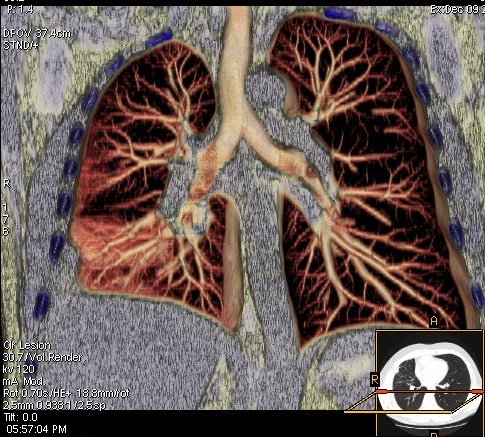

Foto: Aleksandar Ivković Foto: Aleksandar Ivković Foto: Aleksandar Ivković Strašna razlika kod pluća pušača i kovid pozitivne osobe autor: Božica Luković Zdravlje 23. jan. 2021. 12:06 > 23. jan. 2021. 12:15 0 Podeli vest: Radiolog Aleksandar Ivković od početka pandemije daje korisne informacije o svim aspektima kovida 19. On je nedavno uporedio rendgen snimke pluća zdrave osobe, pušača, osobe koja je zaražena gripom H1N1, a onda i osobe koja ima kovid 19. Razlike su zapanjujuće. Podeli vest: Oglas Objavu doktora Ivkovića sa njegovog bloga "Ljudi i ostale laži" prenosimo u celosti."Nedavno sam video u medijima da je neko preneo rdg sliku i razlike kod nalaza zdrave osobe, pušača i bolesnog od kovida 19. Kako nisam baš previše zadovoljan onim što je prikazano, evo kako to izgleda u našoj varijanti. Zdrava osoba CT nalaz kod zdrave osobe podrazumeva da ne postoje nikakvi poremećaji strukture plućnog parenhima, da su krvni sudovi uredni i da nema suženja disajnih puteva, kao i da nema uvećanih limfnih žlezda u hilusima pluća i medijastinumu. Foto: Aleksandar Ivković | Foto: Aleksandar Ivković * Foto: Aleksandar Ivković | Foto: Aleksandar Ivković Zdrava muška osoba mesec dana nakon zapaljenja pluća tokom kovida 19. Nalaz bez nekih posebnih problema iako se naziru tragovi zapaljenja. Snimak u boji je zdrava osoba, nepušač, bez ikakvih bolesti pluća u istoriji. Grip H1N1 Pokazaću samo drastične nalaze kod gripa H1N1, to je znači onaj grip koji je izazvao epidemiju španske groznice i epidemiju 2009. godine koja još uvek nije prestala (svake godine imamo makar 15%). Foto: Aleksandar Ivković | Foto: Aleksandar Ivković * Foto: Aleksandar Ivković | Foto: Aleksandar Ivković * Foto: Aleksandar Ivković | Foto: Aleksandar Ivković * Foto: Aleksandar Ivković | Foto: Aleksandar Ivković Nisu svi pacijenti imali ovakve nalaze, pokazujem one koji su imali tešku kliničku sliku. Kod gripa se sve odvija obično u sedam dana. Kao što se vidi, zapaljenje je bilo jednostrano, uglavnom. Ali kada je dolazilo do pogoršanja, onda je centralno obostrano dolazilo do edema pluća. Pušenje Kod pušača postoje razne varijante nalaza na plućima. U principu nisu tako dramatične kao što su zapaljenja. Nalaz na plućima kod pušača može biti potpuno normalan. Ovo ne pišem zato što podržavam pušenje, naprotiv, veliki sam protivnik, ali iznošenje laži nikada nije dobro. Dve dijagnoze su bitne kao posledica pušenja. Prva je hronična plućna opstruktivna bolest: Foto: Aleksandar Ivković | Foto: Aleksandar Ivković * Foto: Aleksandar Ivković | Foto: Aleksandar Ivković * Foto: Aleksandar Ivković | Foto: Aleksandar Ivković Jasna je razlika u nalazu, posebno na ovim slikama u boji, gde su ta plava polja delovi pluća koji su propali zbog cigareta (može da se uporedi sa zdravim plućima iznad).Druga bolest koja je česta kod pušača je u svakom slučaju karcinom. Foto: Aleksandar Ivković | Foto: Aleksandar Ivković * Foto: Aleksandar Ivković | Foto: Aleksandar Ivković * Foto: Aleksandar Ivković | Foto: Aleksandar Ivković * Foto: Aleksandar Ivković | Foto: Aleksandar Ivković Tkivo koje raste unutar pluća i razjeda ga. Takav je nalaz kod karcinoma pluća. Često je uzrok upotreba cigareta. Kovid 19 O kovidu sam pisao puno puta. Evo nekih slika, radi poređenja. Foto: Aleksandar Ivković | Foto: Aleksandar Ivković * Foto: Aleksandar Ivković | Foto: Aleksandar Ivković * Foto: Aleksandar Ivković | Foto: Aleksandar Ivković * Foto: Aleksandar Ivković | Foto: Aleksandar Ivković Nakon što pacijent bude izlečen od gripa ili kovida 19, pluća se mogu vratiti u normalu.To je razlika u odnosu na posledice upotrebe cigareta. Ovi snimci nisu postavljeni da bi se poredile bolesti, već da bi se ukazalo kako različite bolesti deluju na pluća. I ono što je veoma važno, ako neko dobije jednu od ovih bolesti, ne znači da u toku života neće dobiti drugu.Ne pišem zato smo smatram da sam najpametniji ili najpozvaniji da objašnjavam, nisam kao neki pojedinci ubeđen da samo ja imam znanje i istinu, pišem jer drugi ćute. Pišem jer ima i puno onih koji iznose laži, mora se tome stati na put.A ovi, koji pišu da sam umro, da sam oboleo od karcinoma, ovi koji mi žele da nađem dobro grobno mesto, šta da vam kažem, vi ste mi inspiracija. Svesni ste da sam u pravu i odlično znam da ste već uradili sve da se vakcinišete i mnogi od vas će to uraditi pre mene ali i dalje ćete ubeđivati druge da se ne vakcinišu i da je dobro za njih da se razbole i umru. Ima puno reči za vas u svim našim slovenskim jezicima, znate vi sami šta ste", piše dr Ivković.***Bonus video:https://youtu.be/MWucTT0qBsIPratite nas i na društvenim mrežama:FacebookTwitterInstagram Dr Lukić otkrio spisak svih antibiotika za kovid upalu pluća Zdravlje 0 Dr Žujović: Kako oporaviti pluća posle korone Zdravlje 0 Pet znakova da ti je kovid zahvatio pluća Zdravlje 0 Virusolog Ana Banko ruši veliku zabludu o ruskoj vakcini Emisije 0 aleksandar ivković korona kovid pluća snimak pluća Pratite nas na društvenim mrežama: Koje je tvoje mišljenje o ovoj temi? Učestvuj u diskusiji ili pročitaj komentare Budite prvi koji će ostaviti komentar Pošalji komentar Pročitaj komentare (0)